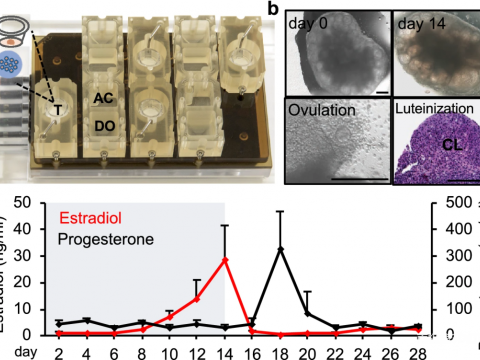

- 美国南卡罗来纳大学Xiao等 | 生物工程女性生殖模型